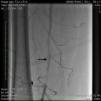

Case reportA 50-year-old Caucasian woman with hypertension, tobacco abuse, and peripheral arterial disease with life-limiting claudication had stents placed in bilateral 80% ostial iliac artery lesions two months previously. She was also noted to have a CTO of the left SFA at the ostium with no obvious stump (Figure 1) which was reconstituting distally via collaterals just above the popliteal artery (Figures 2 and 3). Due to her ongoing symptoms despite optimal medical therapy, it was decided to intervene on the SFA. Since there was no obvious stump of the occluded SFA proximally, we decided to approach the CTO through a retrograde approach.